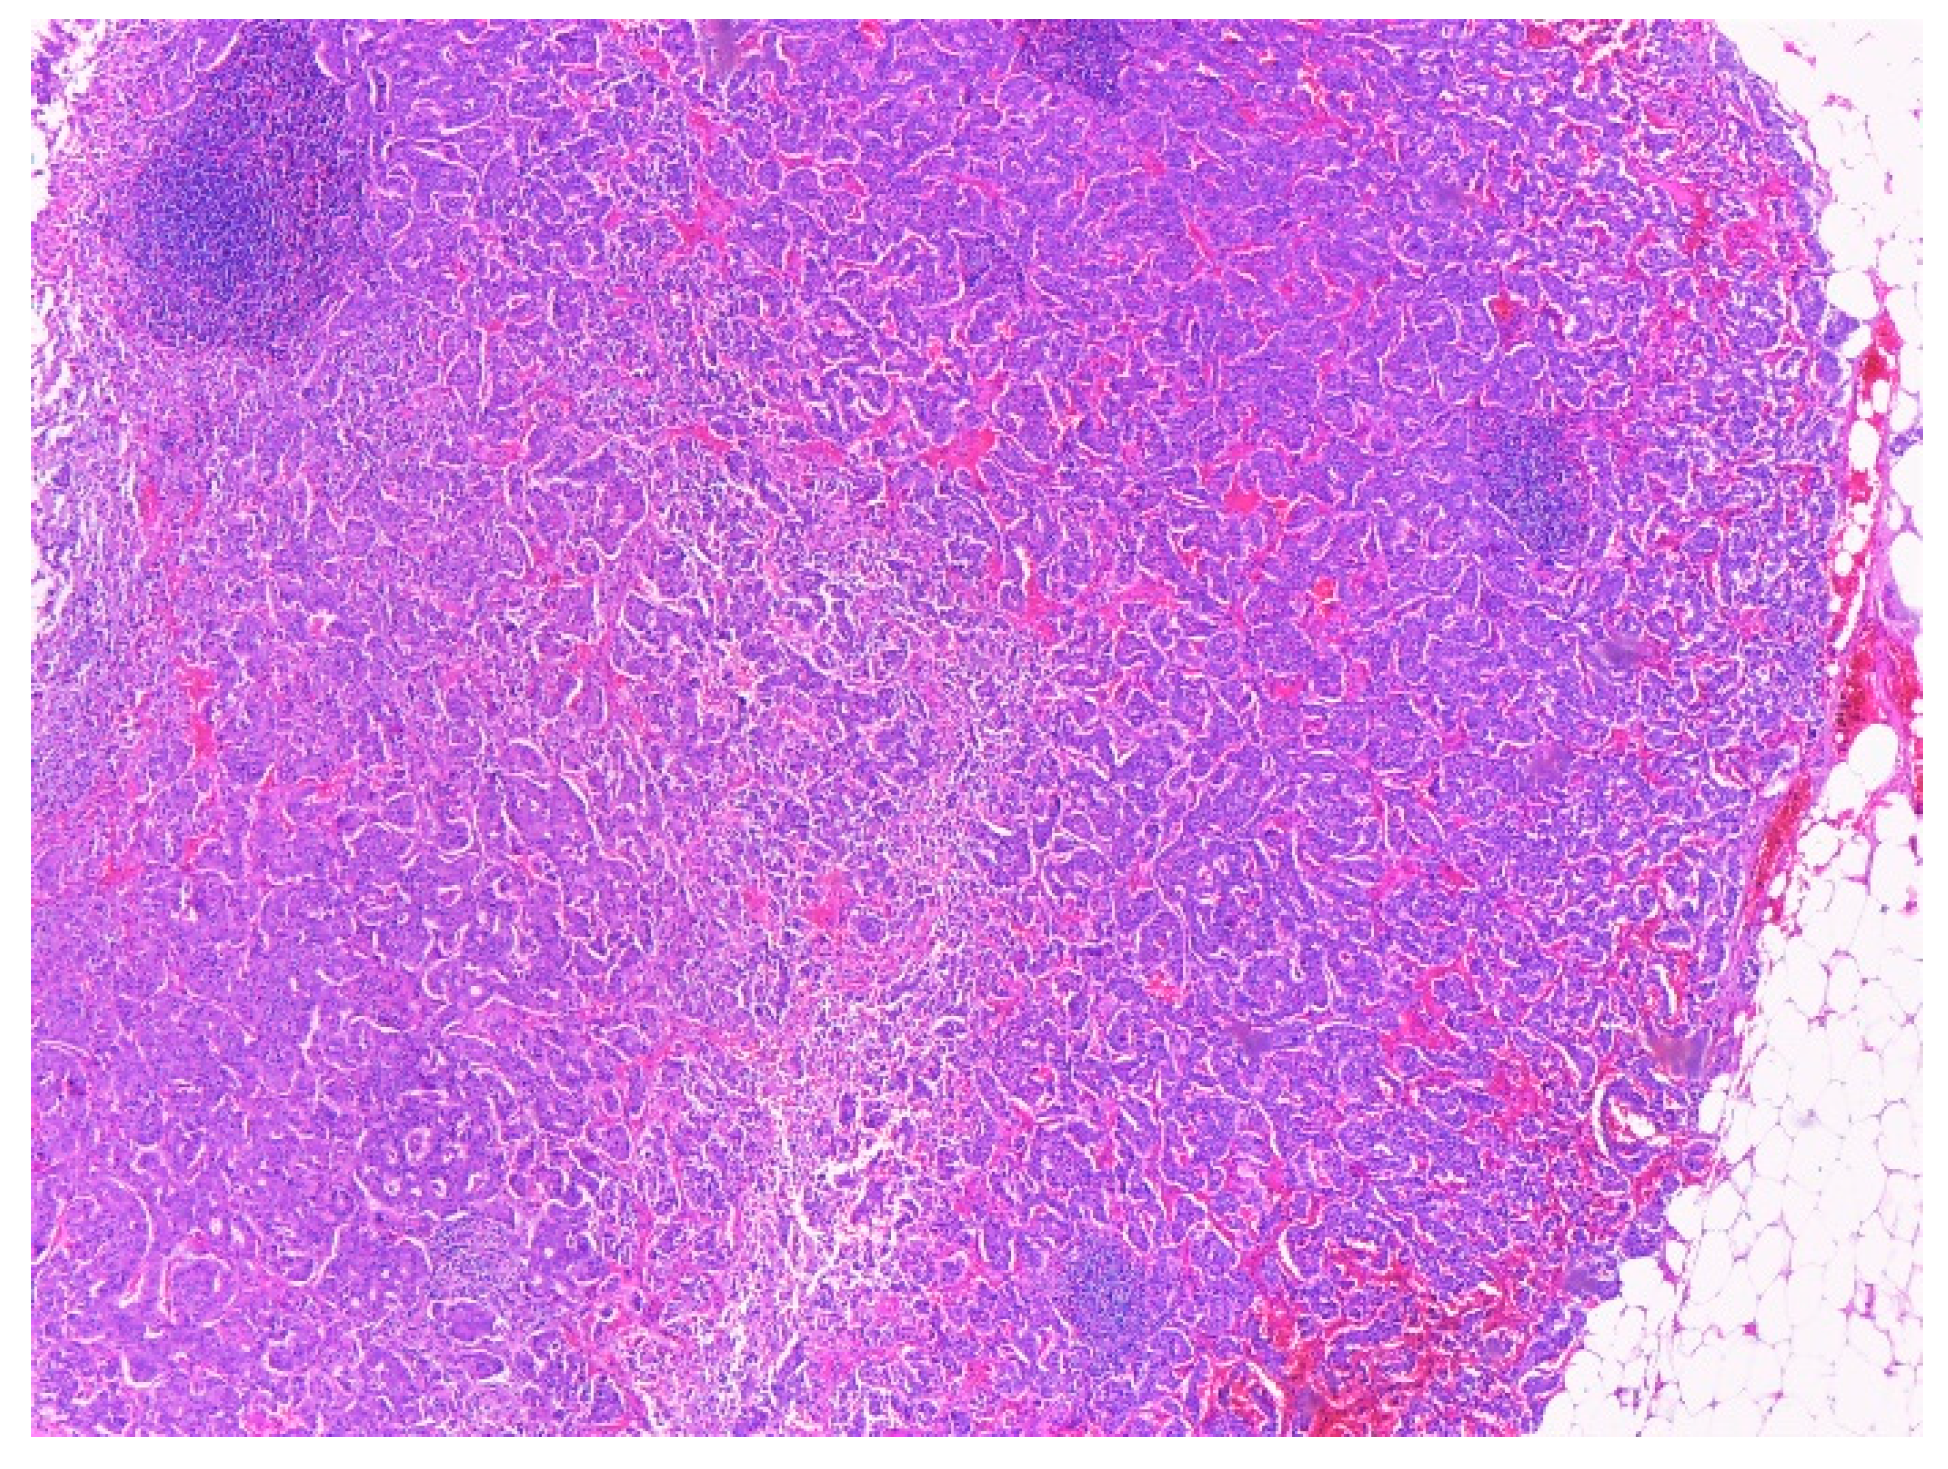

2.4. Histopathological Exam

| Sample | Sample | Sample 1 | Sample 2 | Sample 3 | Sample 4 |

| Aspect | Tumor proliferation with cells containing round, oval, pleomorphic nuclei, and fine granular chromatin. Proliferation covered the entire section and caused partial ulceration of the mucosa that crosses muscular propria layer and extends into the peripancreatic adipose tissue with discrete infiltration of pancreatic acini. Infiltration was clearer after synaptophysin labeling. | Tumor proliferation with atypical cells, fasciculate disposition, elongated nuclei, discrete nucleoli, and pale eosinophilic cytoplasm. The apparent origin of the tumor is muscularis propria | Small intestine sample with tumor proliferation, composed of cells with fascicular disposition, elongated and non- pleomorphic nuclei, pale eosinophilic cytoplasm, rare epithelioid cells. The apparent origin of the tumor is muscularis propria | Sample muscle proliferation with tumor proliferation composed of cells without atypia, fascicular disposition, elongated nuclei, discrete nuclei, and pale eosinophilic cytoplasm | Sample muscle proliferation with tumor proliferation composed of cells without atypia, fascicular disposition, elongated nuclei, discrete nuclei, and pale eosinophilic cytoplasm |

| Tumor cells | CgA-positive SPY-positive Ki67-reduced, maximum 2% | c-kit-positive DOG1 positive SMA-negative | c-kit-positive DOG1 positive SMA-negative CgA-negative | c-kit-positive SMA-negative | c-kit-positive SMA-negative |